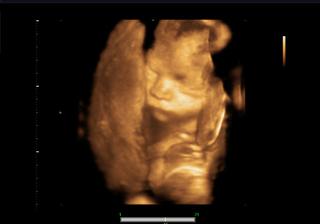

@bettyx no zrovna dobré správy nemám, len mám k tomu iný postoj.. 😠 na poradni som dnes začala špiniť... tak mi doky rovno povedal, že mám nejakú infekciu, a že keď pôjde čerstvá krv, hajde do nemocnice.. 😖 Dal mi hneď lieky do pošvy, Macmiror, k tomu ten znížený kreatinín.. a poslal ma na krčné, lebo mám od malého asi nejakého streptokoka, bolí ma hrozne hrdlo a už týždeň sa trápim. Aby toho nebolo dosť, tak som bola potom u známeho na 4D utlrazvuku a ten mi povedal, že malý má pupočník pod bradou, takže mám sledovať pohyby a ozvi, ak by sa mi niečo nezdalo, utekať do nemocnice.. 😠 Tak už budem ďalšie tri mesiace v pohotovosti.. Tiež mám furt čosi, ale už som si povedala, bude, ako byť má... Ale malý je taký nádherný.. taká som bola šťastná.. Bojím sa veľmi oňho, ale nepočúvam blbé reči... riadim sa vnútorným pocitom... A ten má veľkú vieru, že nám boh pomôže a všetko bude dobré... Prikladám foto 😵